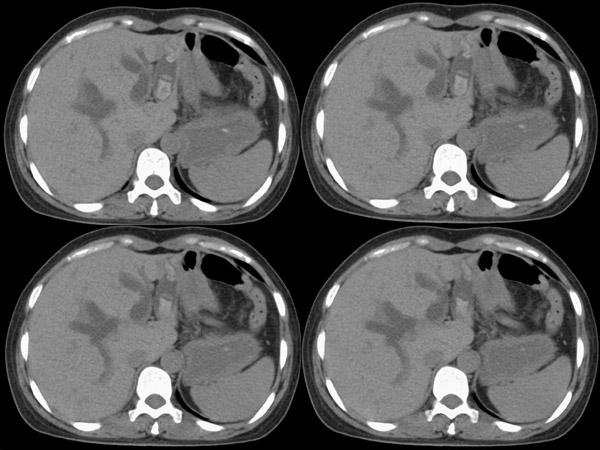

胆总管矢状及冠状重建: